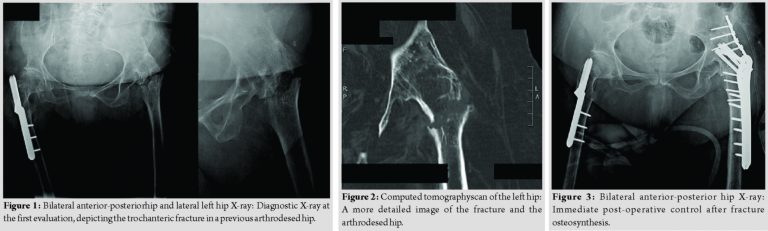

An 83-year-old woman slipped and fell, complaining of the left hip pain and was unable to bear weight. She referred she was submitted to a hip arthrodesis 53 years ago, after an undiagnosed congenital hip dislocation. She also suffered from poliomyelitis and walked around with a cane. The radiographic and tomographic evaluation showed an intertrochanteric fracture in a long-lasting ankylosed hip (Fig. 1 and 2).

After carefully assessing scientific evidence and discussing the appropriate treatment strategy, the patient was prepared for surgery. She was positioned in lateral decubitus and a lateral approach was used, centered on the great trochanter. The fracture was exposed and fixated with two plates. One proximal locking femoral plate, with 6mm×4.5 mm cortical and 4mm×6.5 mm cannulated screws, was applied to the head and proximal femur. Expecting a great stress in the fracture site, this construction was reinforced with a 3.5 mm pelvic reconstruction plate, with 8mm×3.5 mm cortical screws, spanning from the iliac wing to the proximal femur (Fig. 3 and 4). Due to the poor bone quality and the unusual long lever arm, the patient was not permitted to walk until 3 weeks after the intervention (Fig. 5) and only partial weight-bearing afterward. Bone healing occurred after 3 months, allowing the patient to walk with a single cane and full weight-bearing (Fig. 6).